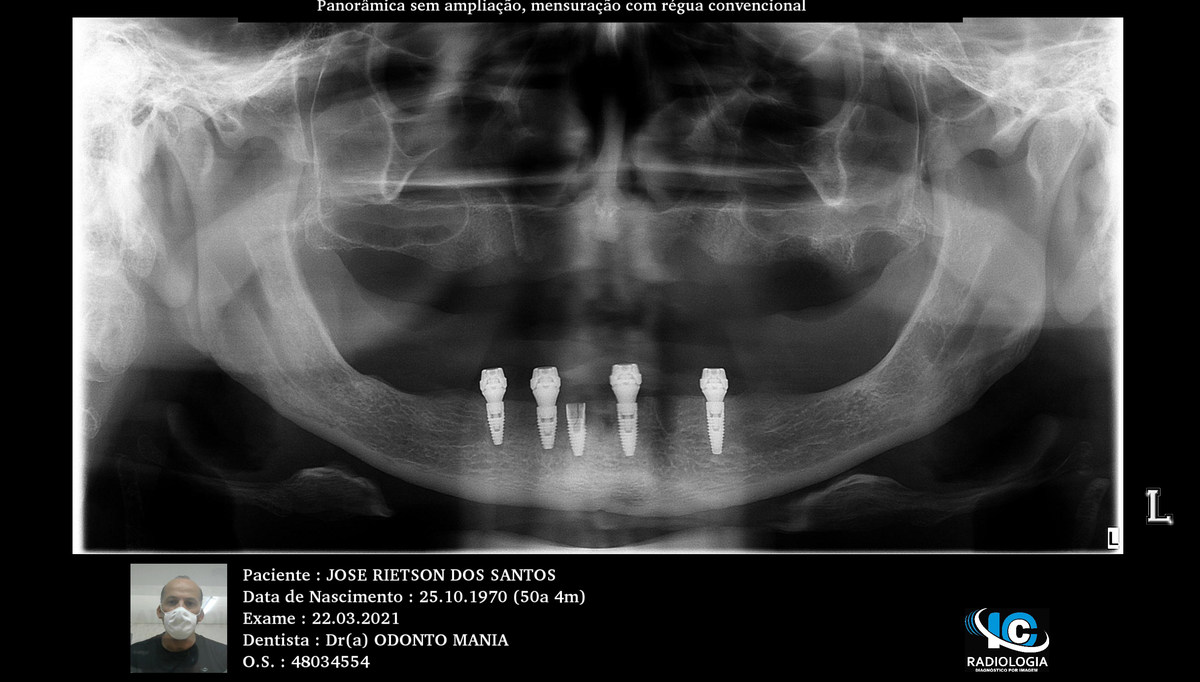

PRÓTESE TOTAL FIXA EM IMPLANTES

J.R.S.